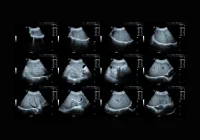

Muscle volume is a critical determinant of strength and an important marker for neuromuscular health, with applications ranging from tracking training adaptations to diagnosing conditions such as sarcopenia and muscular dystrophy. Magnetic Resonance Imaging (MRI) remains the reference standard for such measurements, offering high accuracy and detail. However, MRI is costly, time-consuming and less accessible in many settings. Three-dimensional ultrasonography (3DUS) offers a more affordable and patient-friendly alternative. Recent research has evaluated a custom 3DUS system for assessing lower limb muscle volume, focusing on its validity, reliability and comparability to MRI.

While reliability was strong, direct comparison to MRI revealed systematic underestimation of muscle volume by 3DUS. In the initial protocol, differences ranged from −10% for tibialis anterior to −33% for gastrocnemius medialis, with the highest agreement for tibialis anterior and the lowest for the gastrocnemii. The underestimation was attributed mainly to probe pressure on the skin and narrow sweep distances during scanning, which can distort muscle geometry and lead to reconstruction artefacts. To address this, the acquisition protocol was adapted in a second phase: sweep widths were increased from 3.5 cm to 6 cm, and a 1 cm gel layer was used to minimise probe contact with the skin. This modification reduced the mean difference between 3DUS and MRI by approximately 70% for the biceps femoris and vastus lateralis. Although the discrepancies remained higher than those reported in some previous literature, the improvement demonstrated that protocol refinement can meaningfully enhance comparability.

To separate methodological from biological sources of error, the team conducted phantom experiments using volumes closely matching human muscle sizes. Both MRI and 3DUS measured the phantoms with high accuracy, showing only small differences from the known volumes. Agreement between the two imaging modalities for phantom scans was high, with differences of less than 3% in most cases. These findings confirmed that both MRI and 3DUS can produce precise measurements under ideal conditions without probe pressure artefacts. This reinforces the conclusion that in vivo discrepancies are primarily due to scanning technique rather than limitations of the imaging technologies themselves. Furthermore, the study’s openly shared methodology, including detailed setup specifications and code, provides a valuable resource for reproducibility and adoption in other laboratories. Standardisation across research groups could help address the variability seen in muscle volume measurements in the literature, where differences in equipment, software and acquisition protocols make direct comparison challenging.